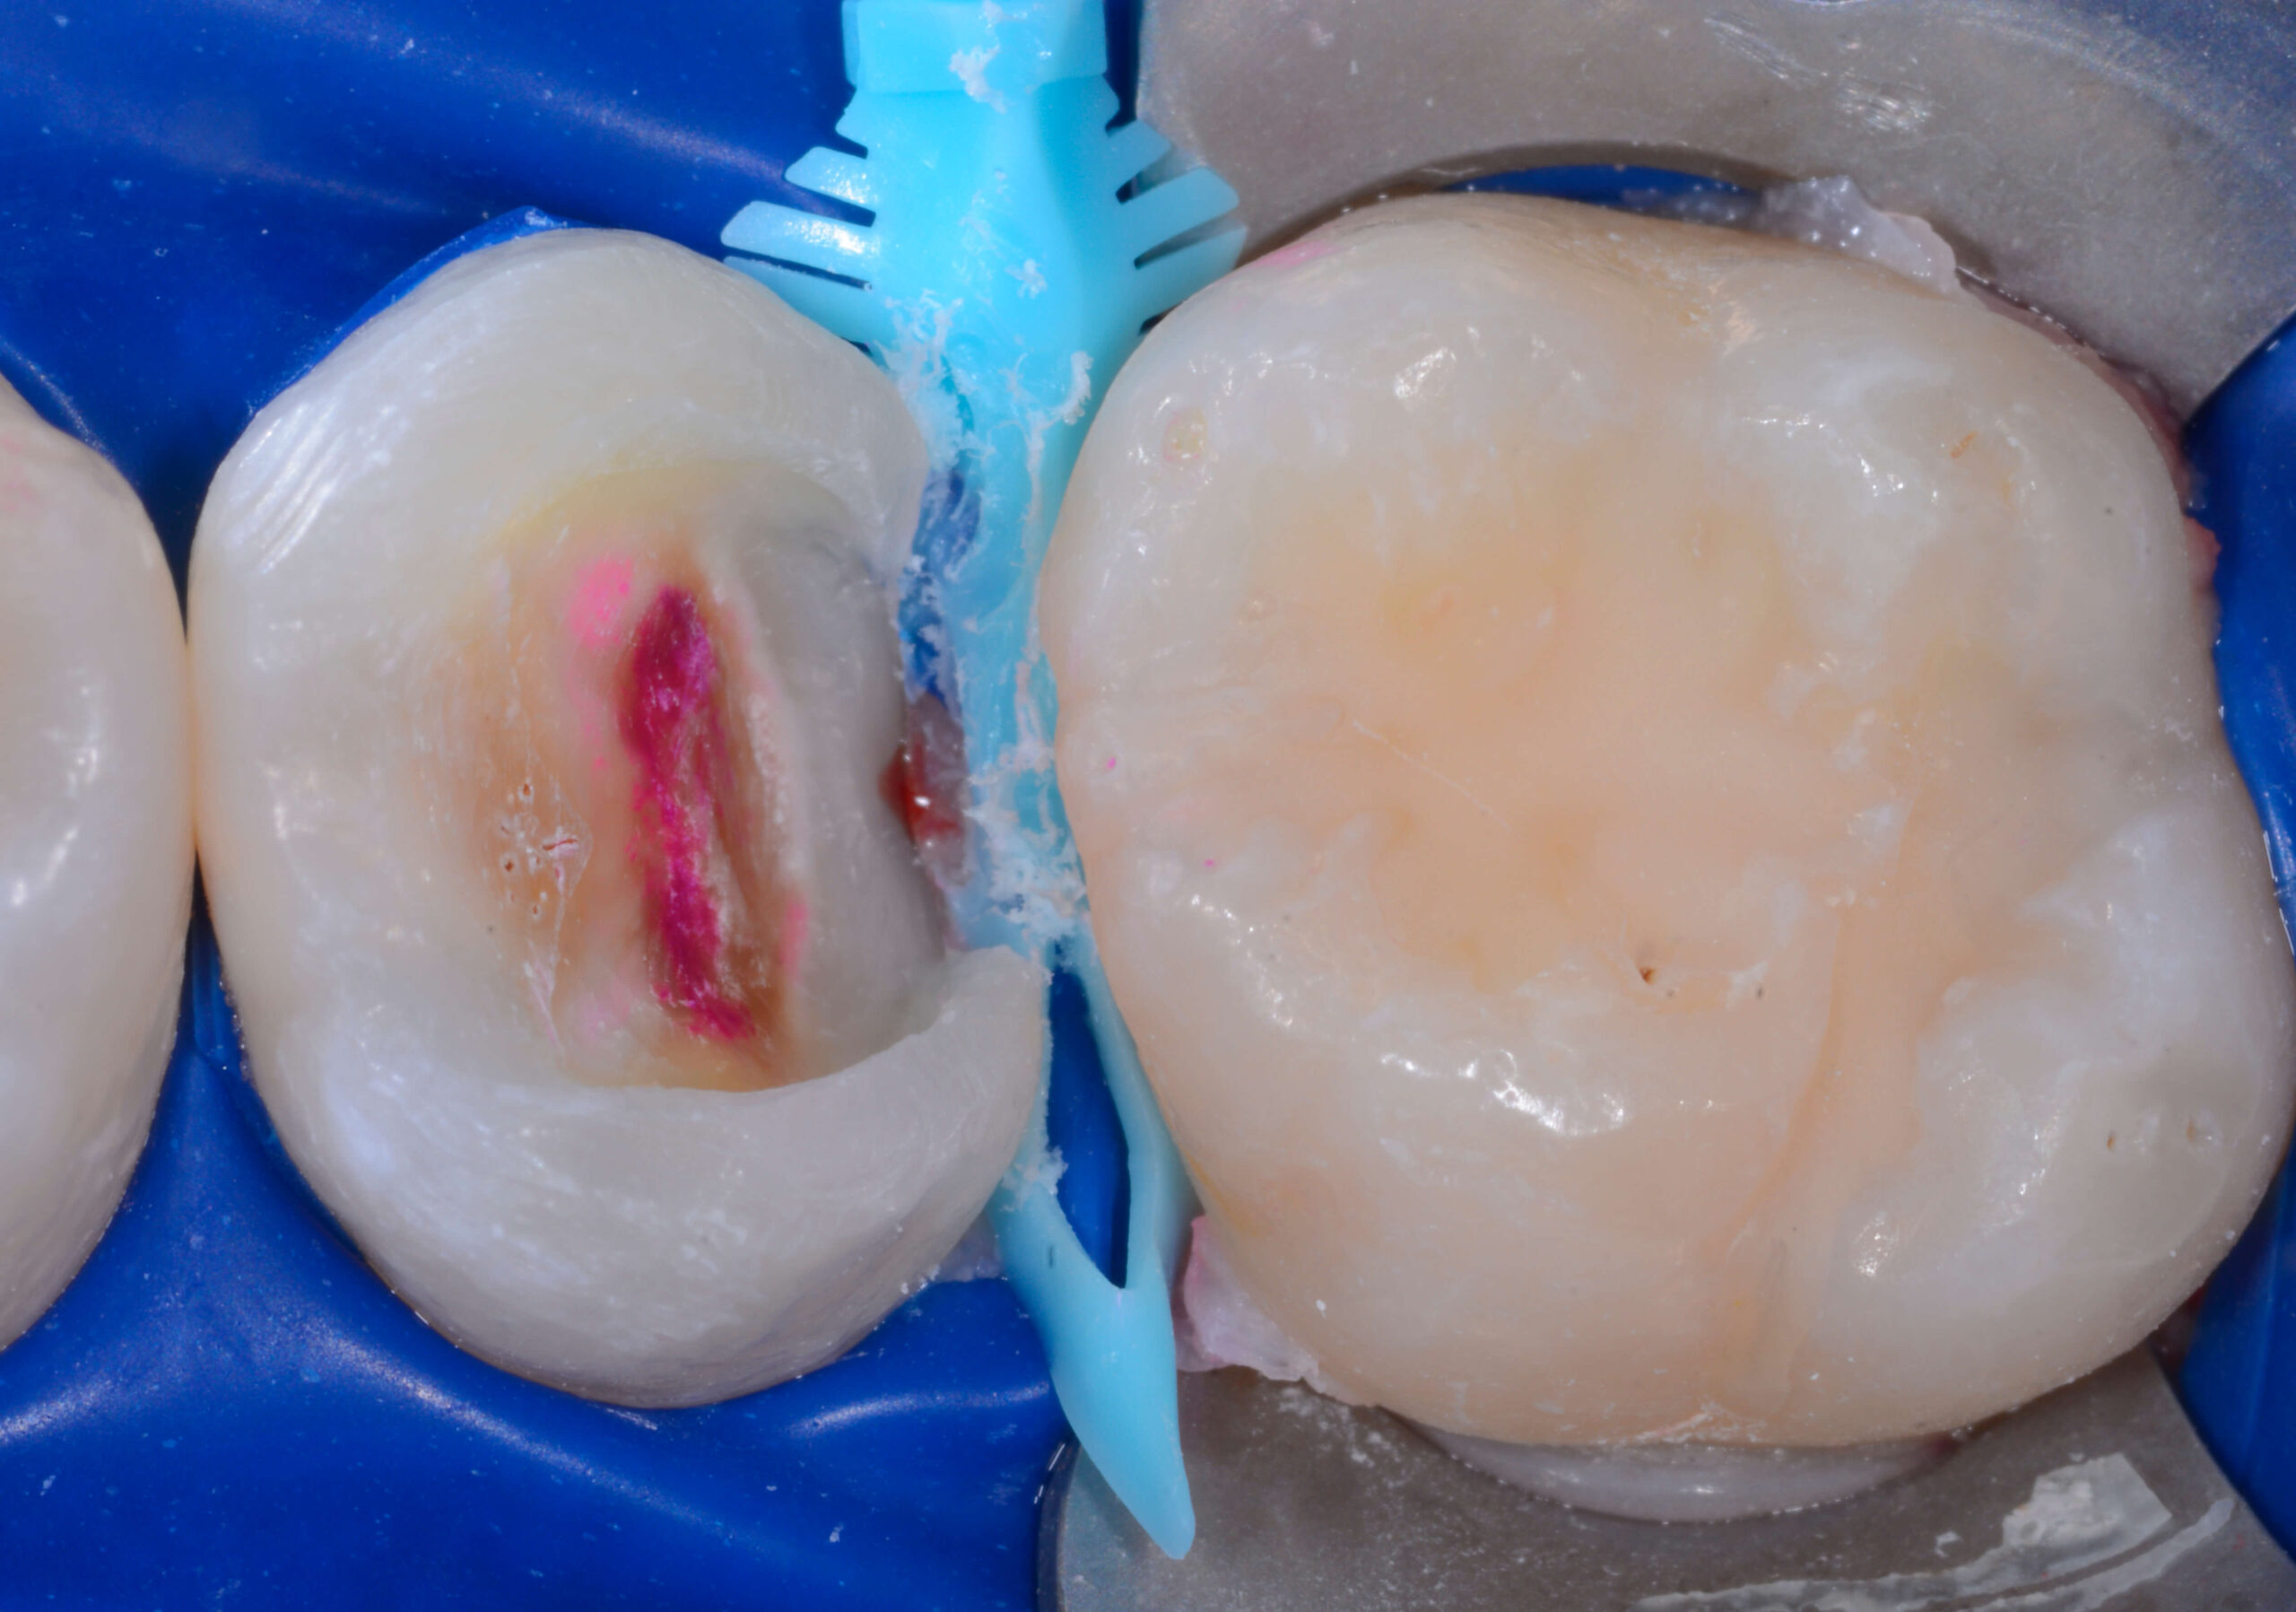

After disclosing solution is applied, the Bioclear Blaster thoroughly removes biofilm leaving the tooth ready for composite restorations.